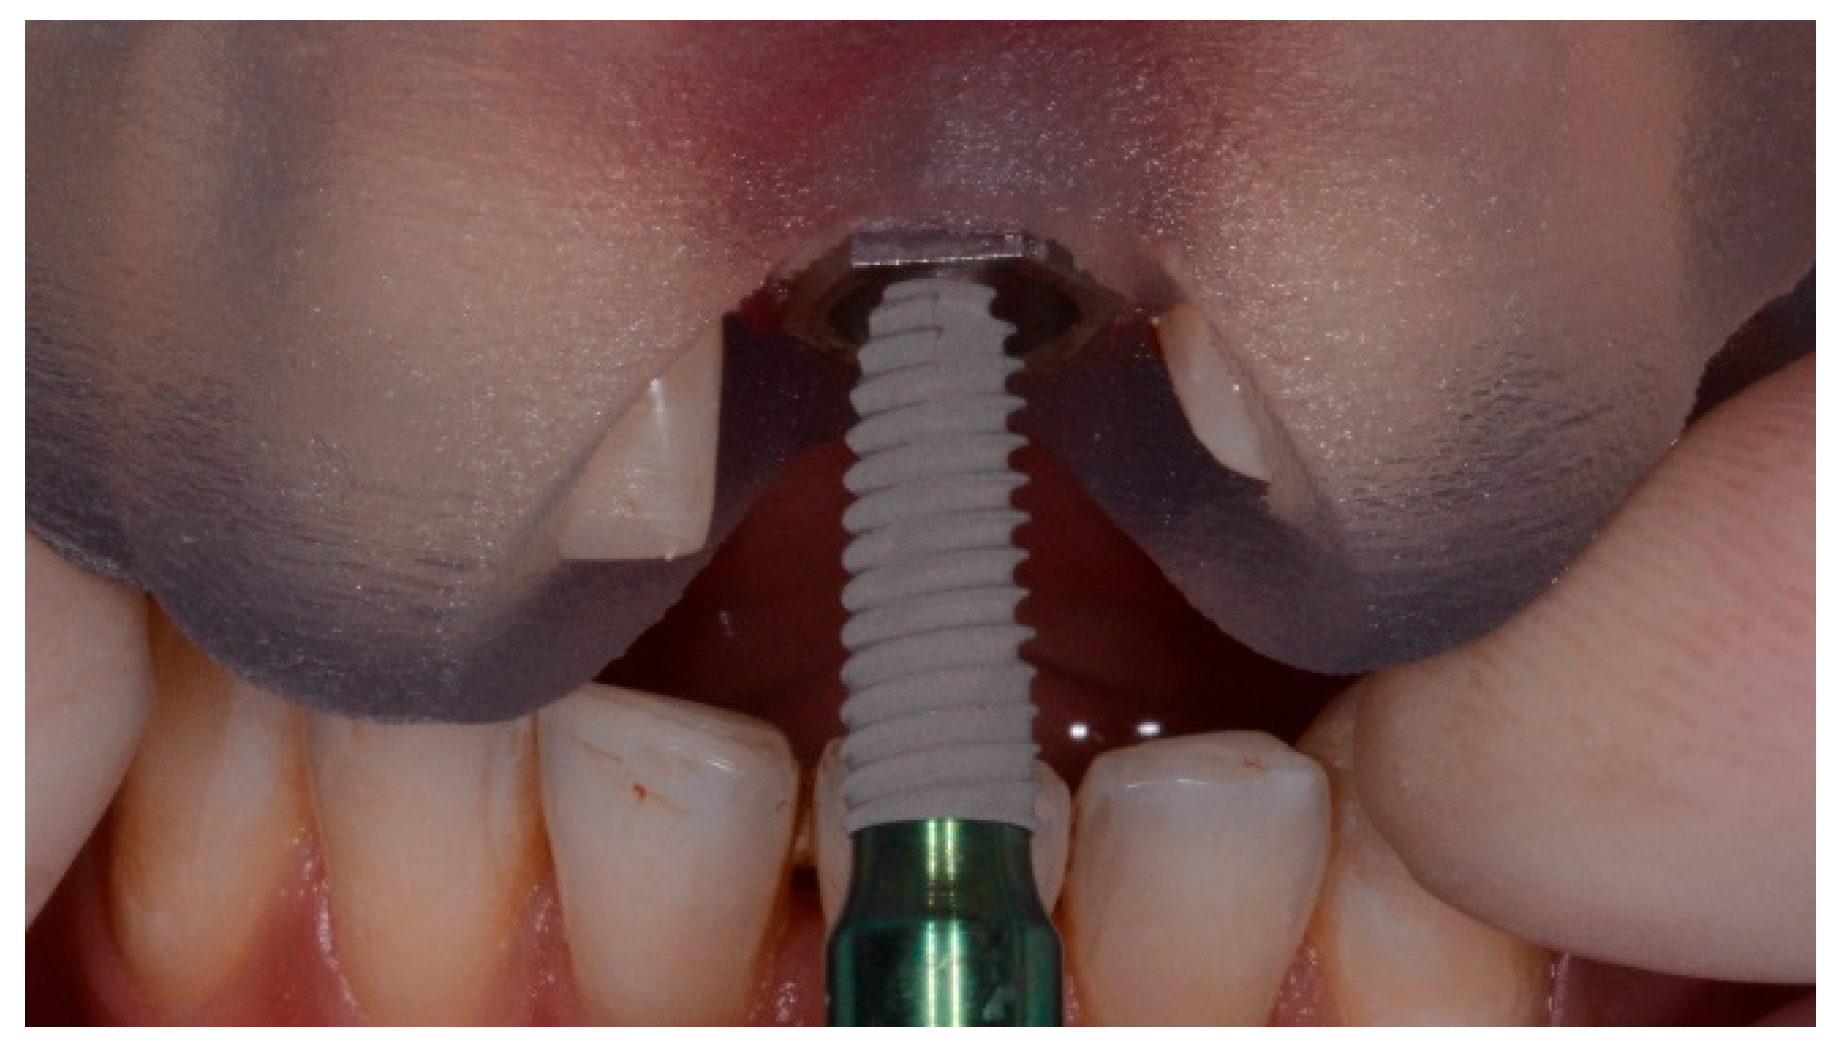

Both templates were able to achieve successful results, nevertheless, the null hypothesis that there would be no differences in implant accuracy between templates with or without metallic sleeves was partially rejected in favor of the hypothesis of differences. In fact, there was not a statistically significant difference in the horizontal position between the virtual and planned implant position, but there were statistically significant differences in angle and vertical discrepancy between the groups, with more accurate values for tubeless templates. A possible explanation is that the holes within the templates without metallic sleeves can be customized compared with standard metallic sleeves. On the contrary, the metallic sleeves cannot be modified in case of collision with soft or hard tissues (Figure 7). Hence, a flap must be elevated to avoid misfitting of the surgical template during its insertion. Otherwise, templates without metallic sleeves can have a customized fitting to the patient’s anatomy, reducing the risk of losing accuracy.

Figure 7. Collision between the mesial side of the metallic sleeve and the patient’s anatomy.